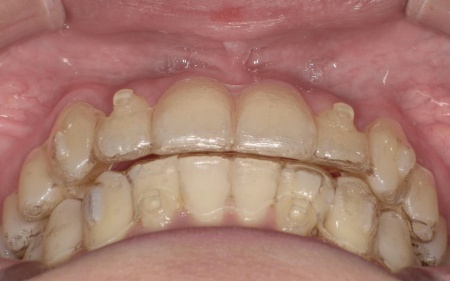

歯並びを改善する方法として、透明なマウスピースを段階的に交換しながら歯を動かしていくインビザラインコンプリヘンシブパッケージによる矯正治療を提案し、同意いただきました。

インビザラインコンプリヘンシブパッケージは装置が透明で目立ちにくく、取り外しができるため食事や歯磨きがしやすい点がメリットです。

まず、患者様専用のマウスピースを作製し、1日一定時間装着していただくようご案内しました。

マウスピースは定期的に新しいものへ交換しながら、少しずつ歯を移動させています。

治療と並行して、歯と歯の間にスペースを作るためのIPRを適切なタイミングで実施しました。また、噛む力が強い傾向が見られたため、奥歯の噛み込みを抑え、歯をスムーズに動かすために「バイトランプ」と呼ばれる小さな突起をマウスピースの上の前歯の裏側に設置しています。